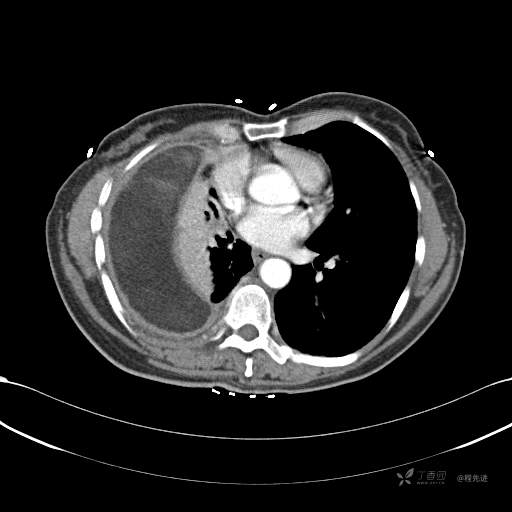

患者性别:女

患者年龄:51岁

简要病史:胸闷半年